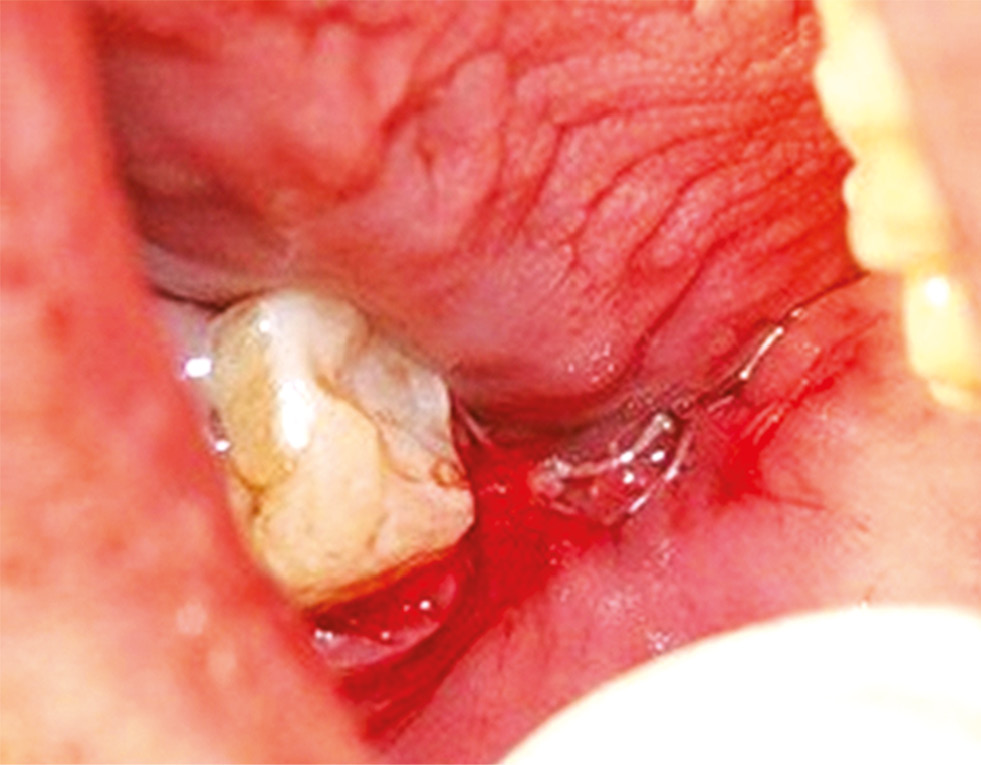

Отслаивали слизисто-надкостничный лоскут. Для предотвращения послеоперационных осложнений и уменьшения травмы при удалении нижних третьих моляров использовали прямой хирургический наконечник по принципу максимального сохранения костной ткани. Выполняли сепарацию коронковой части и корней зуба. Щипцами, прямым или угловым элеватором вывихивали зуб (рис. 2).

Рис. 2. Дистопированный и ретинированный зуб 3.8.

Fig. 2. Dystopian and retinated tooth 3.8.